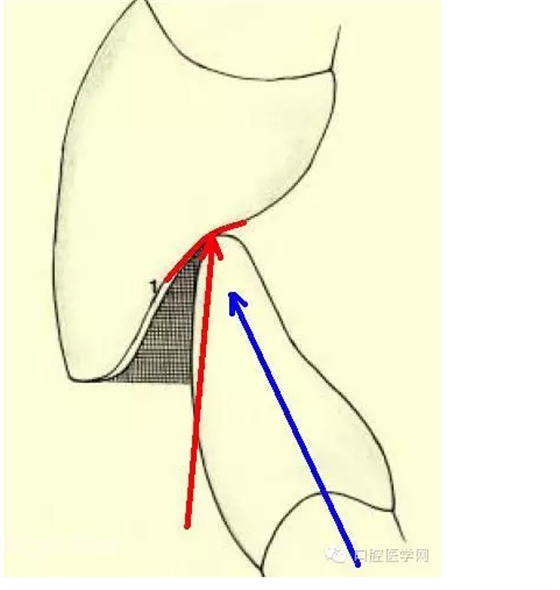

我想對(duì)于第二類很多人不是很明白,這里我解釋一下。對(duì)于天然牙齒也好,還是修復(fù)體也好,咬合力必須是垂直的。而牙齒是不能承擔(dān)側(cè)向力。這點(diǎn)我想搞種植的醫(yī)生是最清楚不過了。(這是我制作的HE學(xué)幻燈中的一張圖片)

當(dāng)然,有些人對(duì)前牙的受力會(huì)有疑問,因?yàn)槎鄶?shù)人認(rèn)為前牙是側(cè)向力,比如前牙做的引導(dǎo)。其實(shí)咬合中有一個(gè)概念叫Centric Stops(正中止),這一方面是指每個(gè)牙齒都有應(yīng)該它咬合的正確接觸點(diǎn),另一方面是說,人在CO(尖窩交錯(cuò))位時(shí),下頜不能有滑動(dòng),以作為肌肉和關(guān)節(jié)的保護(hù)。而前牙同樣有這樣一個(gè)位置。前牙正確的接觸是在前牙舌隆突上,有一個(gè)類似臺(tái)階的形態(tài),當(dāng)與下前牙的切緣接觸時(shí)會(huì)形成向一個(gè)延牙齒長軸方向的受力,同時(shí)這又限制了下頜的運(yùn)動(dòng)范圍(紅線)。如果舌側(cè)沒有這樣一個(gè)合適的咬合位置,限制下頜,下頜會(huì)形成一個(gè)向前的力(藍(lán)線)。